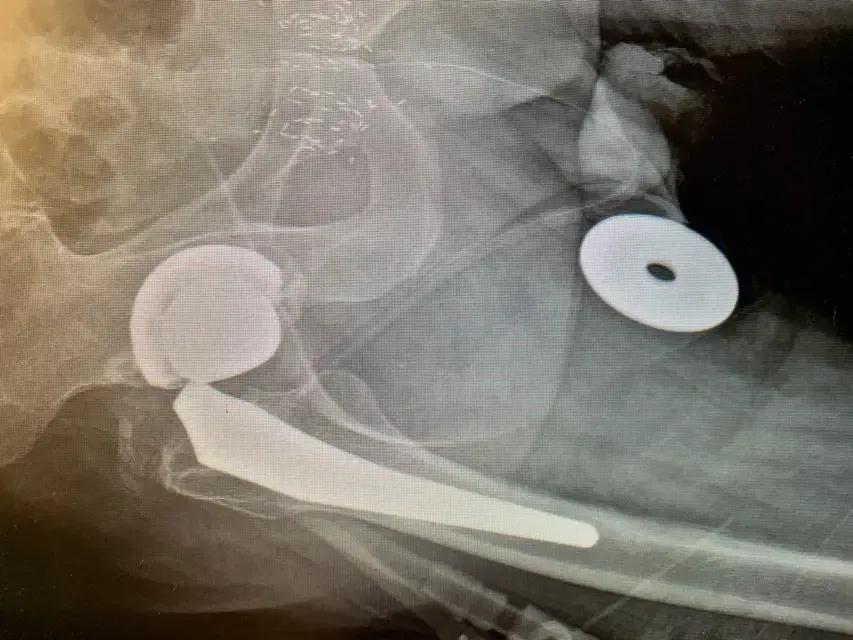

Plain film radiographs revealed thinning and “penciling” of the neck of the femoral component, indicating likely fretting corrosion at the trunion – also known as “trunnionosis”.

In fact the radiographs suggested the trunion had become so corroded that it had fractured. Further inquiry revealed the type of component used in the initial replacement surgery has since been shown to suffer from this phenomenon at a higher rate than others – though this was not known at the time.